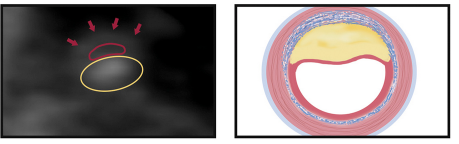

Plaques à Risque

Remodellage positif

Core lipidique <30 HU

Napkin ring sign